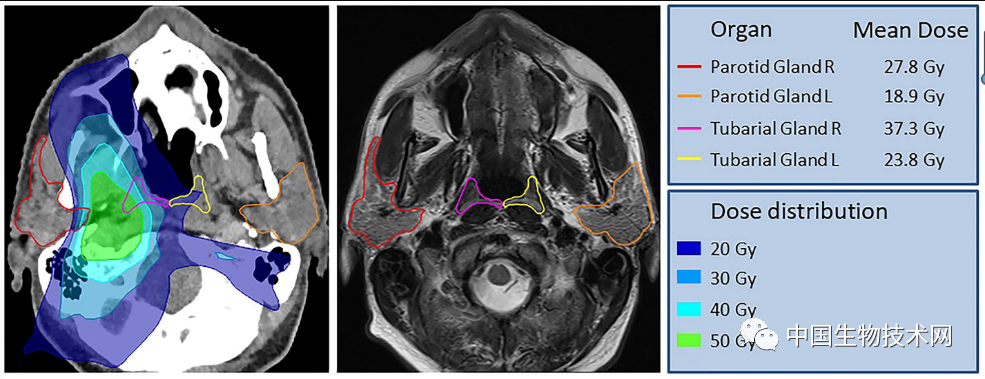

此外,使用前瞻性收集的723例头颈部癌症患者队列的临床数据,研究人员回顾性研究了放疗对流涎和吞咽的影响。结果表明,放射线输送至“管状腺”后会给患者带来更大的并发症。因此,该研究结果不仅有益于未来的肿瘤学,而且似乎支持这个被忽视的神秘“未知实体”的结构确实是唾液腺。

不过,该团队承认,还需要对更大、更多样化的人群进行更多的研究来验证他们的发现;但他们说,这一发现为癌症患者接受放疗前提供了指导,因为唾液腺非常容易受到放疗的损害。在接受放疗的患者中保留这些腺体可能会为其提供改善生活质量的机会。